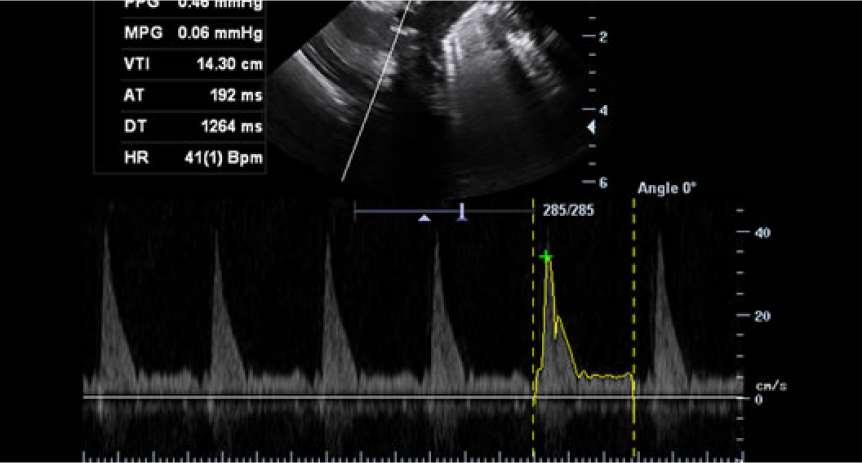

Galería de imágenes

Galería de imágenes